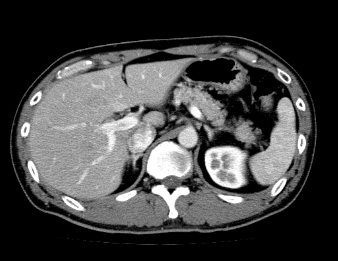

造影検査

造影剤を使用する検査で、造影剤は主に腕の静脈から注射をします。注射した造影剤は全身の臓器に分布していき、血管や臓器が白く染まります。そのため、単純検査よりも血流の状態や、血管、臓器の状態がより詳しく画像化されます。